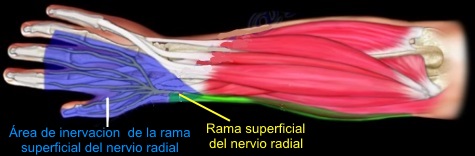

Síndrome de Wartenberg,

descrito en 1932, es el atrapamiento esencialmente de la rama

sensitiva superficial del nervio radial.

El sitio anatómico de compresión corresponde al

tránsito del nervio de su posición submuscular debajo del supinador

largo a su posición subcutánea en el extensor radial largo del

carpo. Especialmente con la pronación, estos 2 músculos pueden crear

un efecto como de tijera comprimiendo el nervio sensitivo radial.

Síndrome de

Wartenberg

Los pacientes con el diagnóstico de síndrome de

Wartenberg se quejan de dolor y parestesias en la superficie radial

dorsal del antebrazo con irradiación al dorso del pulgar y del

segundo y tercer dedos. Con frecuencia refieren aumento de los

síntomas con el movimiento de la muñeca o aparecen cuando se

aprietan los dedos pulgar e índice. Estos pacientes presentan la

prueba de Tinel positiva cuando se percute sobre el ligamento

carpiano palmar. El paciente refiere la sensación como un pinchazo o

una descarga eléctrica sobre la estiloides radial. Al tratarse de un

nervio sensitivo, hay trastornos sensitivos, pero no existe atrofia.